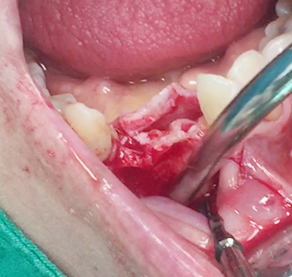

Implants/Bone Grafting

Simultaneous bone graft and implant placement